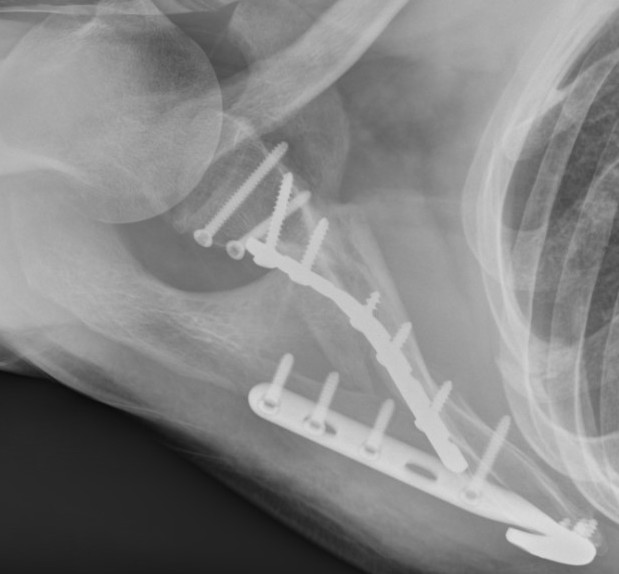

![]() |

Technique

Plates

- lateral border scapula

- scapula spine

- medial border scapula